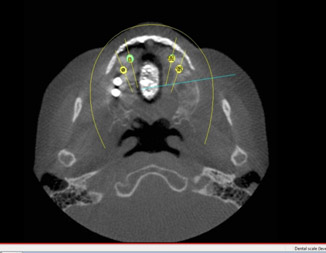

In patients with deeply impacted wisdom teeth, or when there is evidence of pathology, such as bone cysts or tumors, or if there is question about bone anatomy regarding a dental implant, cone beam cat-scan technology may be recommended in addition to the panorex. This helps the oral surgeon to further assess the position of the area of interest, the size of related defects, and the proximity of vital structures, such as sinuses or nerves, etc.

Finally, 3 D scanning is the latest in digital technology involving radiography. With 3D technology, we are able to appreciate boney anatomy on a much more comprehensive scale. With 3 D scanning, the ability to make surgical guides based on the scans to place dental implants accurately. 3D scanning also allows the surgeon to make reconstruction and orthognathic surgery much easier giving access to computer modeling software to recreate the facial bones.